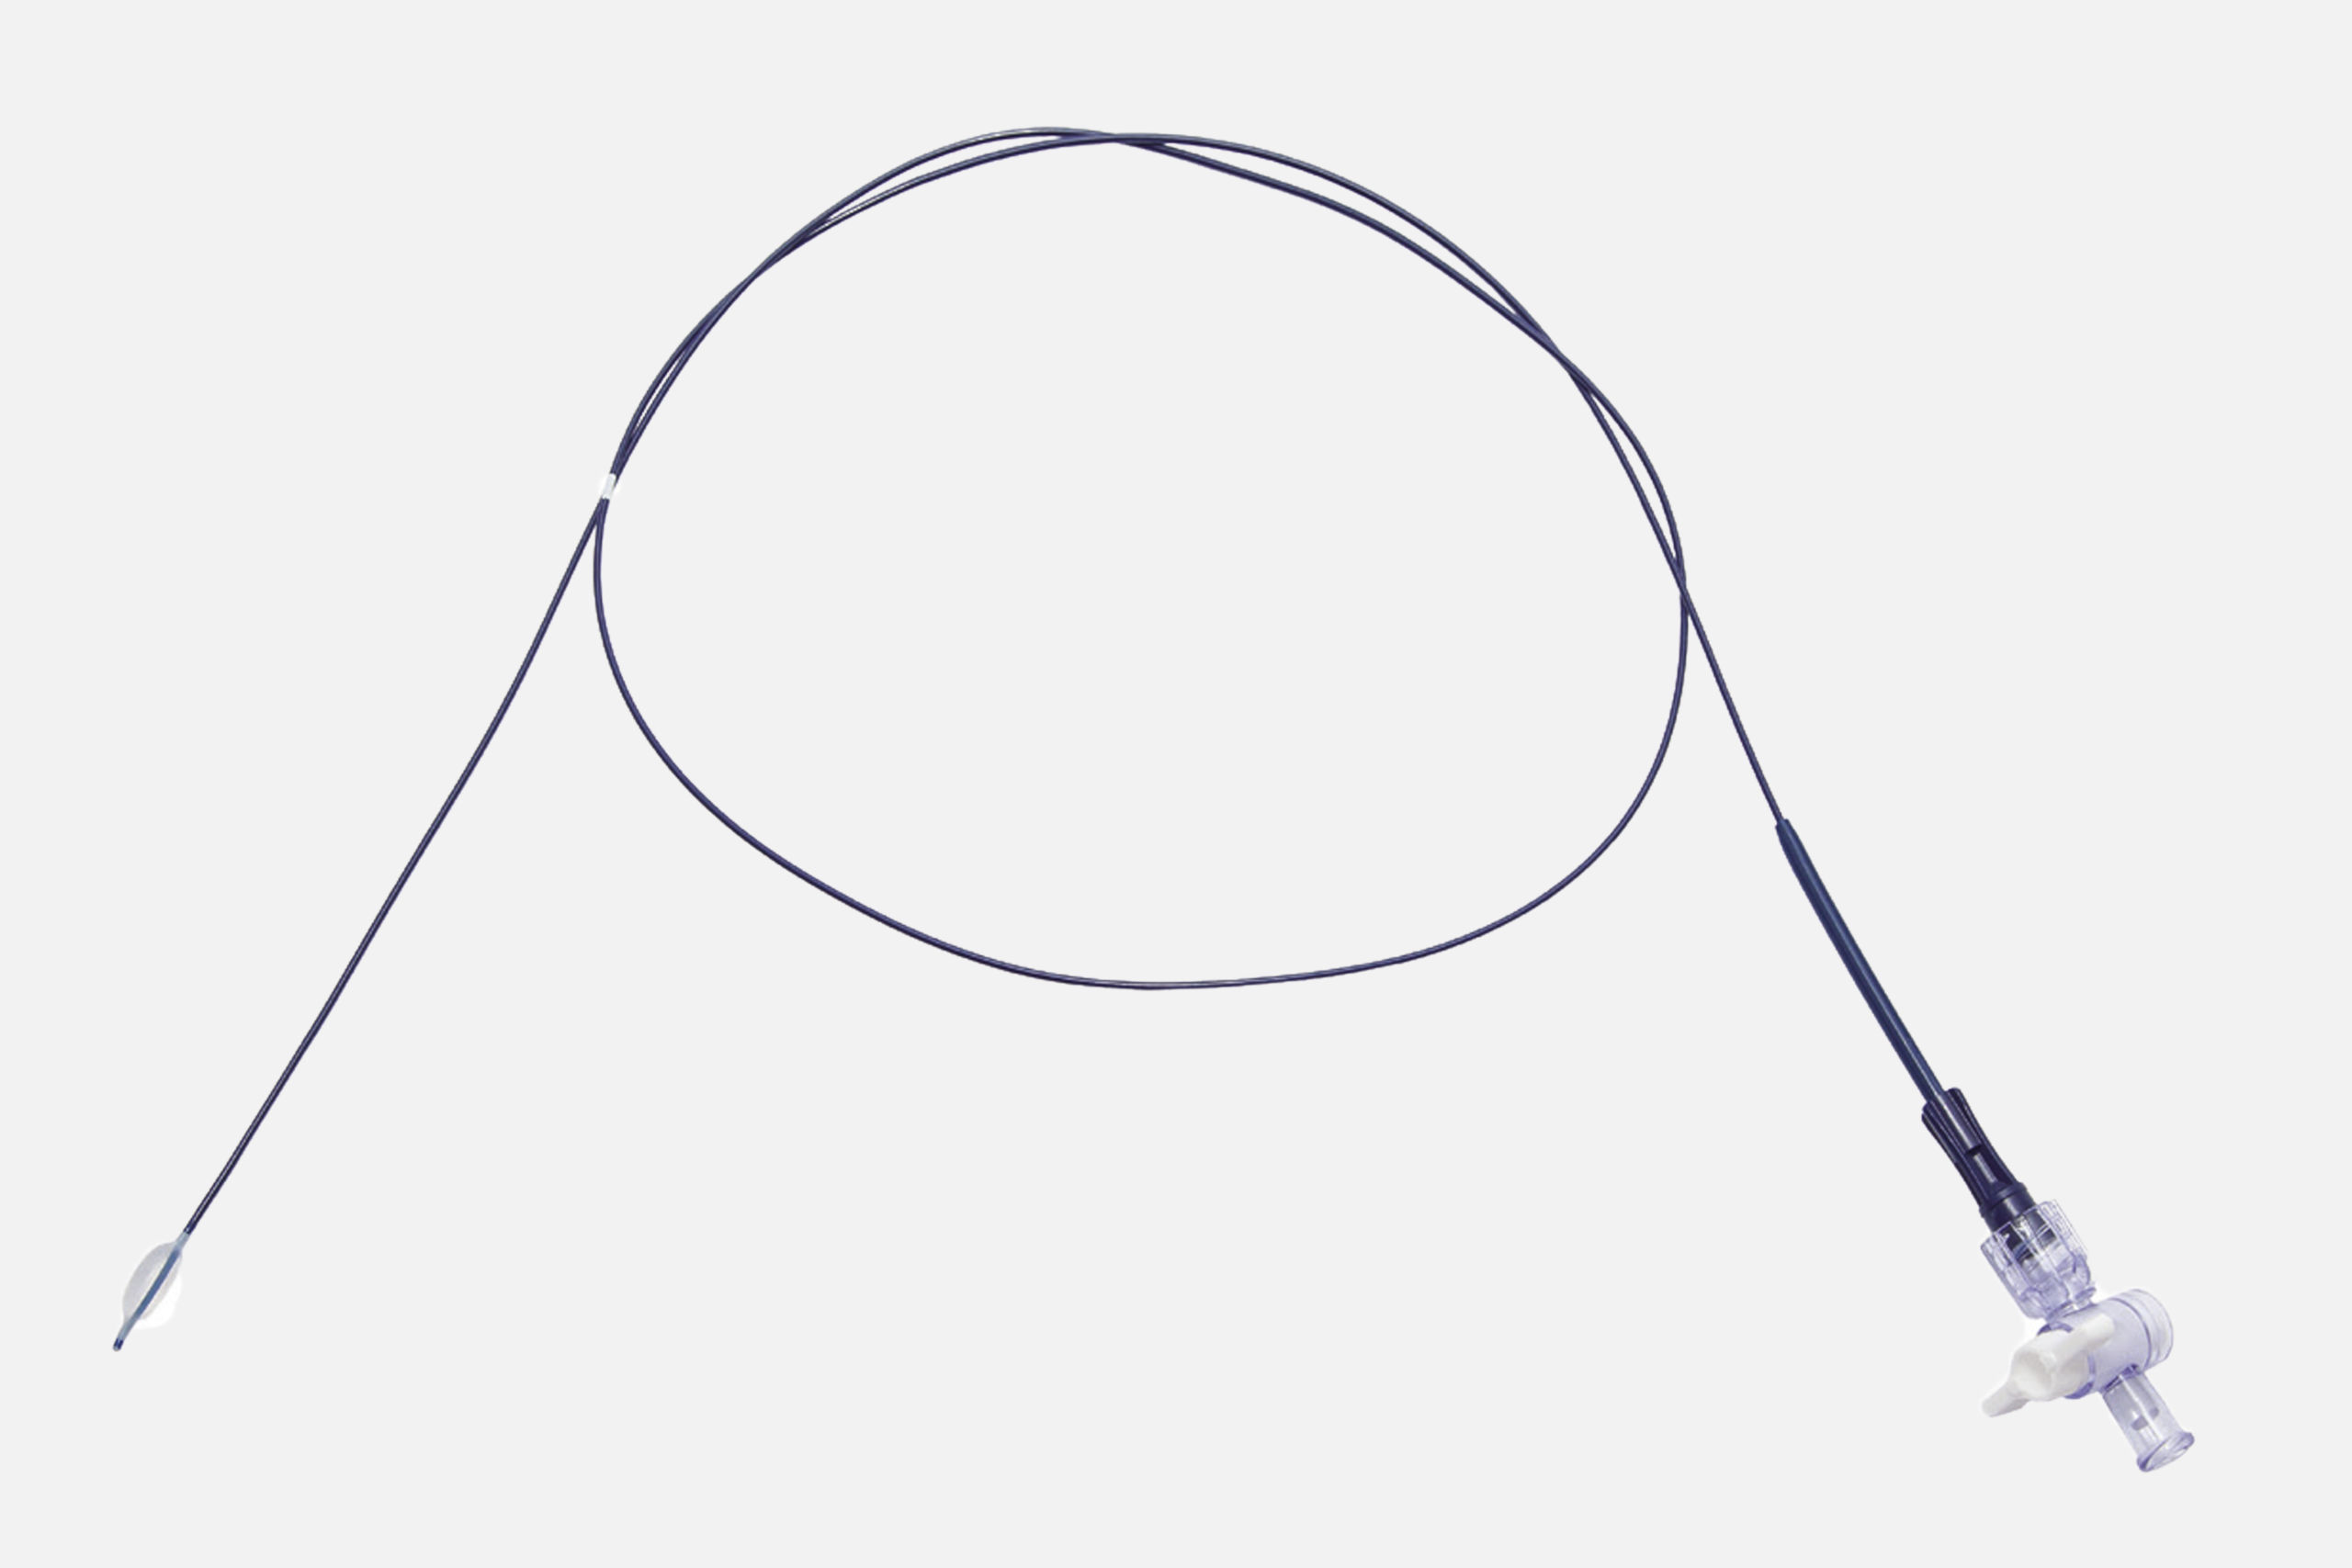

Es un catéter con balón hinchable para adhesiolisis durante la epiduroscopia (IESS). Este dispositivo está diseñado y certificado para su uso junto al catéter guiado por imagen Resascope en el espacio epidural. Éste presenta en su parte distal un balón, que debe inflarse con suero salino accionando la jeringa que encontraremos en el kit y se une al catéter en la parte proximal con una conexión Luer Lock.

Es un catéter con balón hinchable para adhesiolisis durante la epiduroscopia (IESS). Este dispositivo está diseñado y certificado para su uso junto al catéter guiado por imagen Resascope en el espacio epidural. Éste presenta en su parte distal un balón, que debe inflarse con suero salino accionando la jeringa que encontraremos en el kit y se une al catéter en la parte proximal con una conexión Luer Lock.